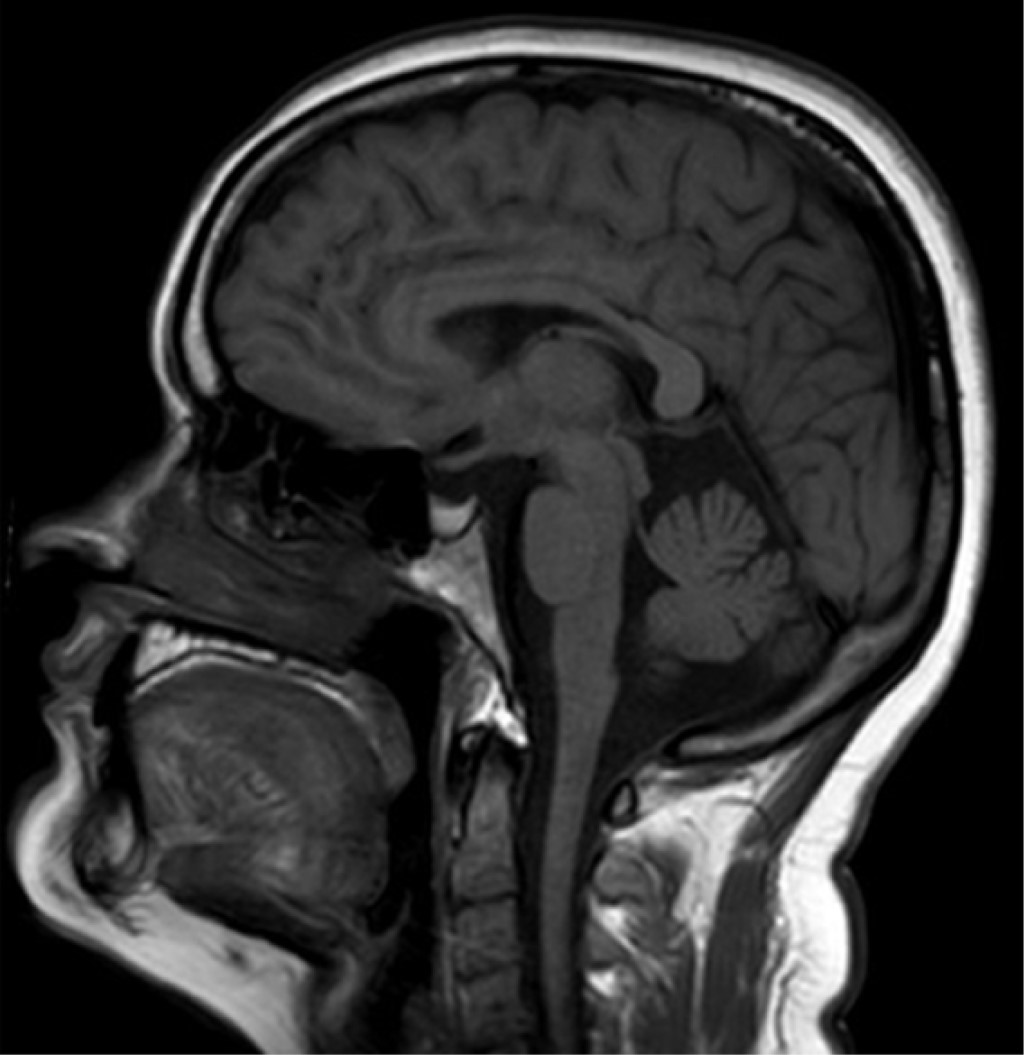

Durante la estancia hospitalaria de 17 días la paciente recupera parcialmente su expresión verbal y fuerza; mantiene un puntaje en la NIHSS de 7 y en la escala modificada de Rankin de 2 al egreso. En la imagen de resonancia magnética nuclear cerebral durante la hospitalización no se documentó crecimiento tumoral ni evidencia de sangrado intratumoral posterior a la trombólisis (Figura 4). En los estudios de estratificación se documenta que la causa del infarto es indeterminada. Se egresa a la paciente con prevención secundaria con monoantiagregación con ácido acetil salicílico y atorvastatina.

Figura 4